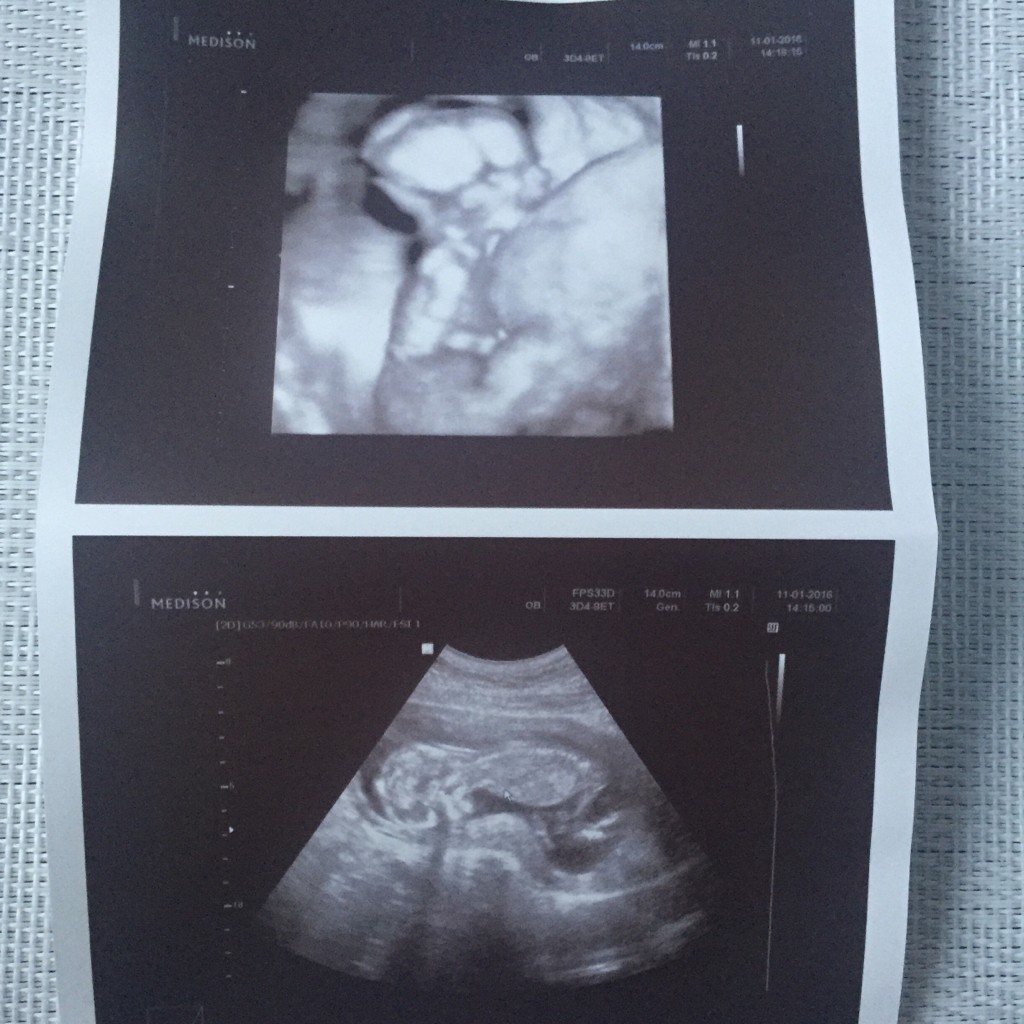

My już po wizycie u lekarza, wszystko superdzieciątko zdrowe, lekarz nie widział żadnych nieprawidłowości, powiedział, że ciąża jest wręcz książkowa

Maluszek fikal na usg, ssał kciuka, machal rączkami i nóżkami

dostaliśmy chyba z 10 zdjęć

coś tam mu dyndało między nogami, ale mamy się nie nastawiać, bo mogą to być wargi sromowe. Ważne ze ma dwie nóżki, dwie rączki i wszystko na miejscu

Jestem bardzo szczęśliwa